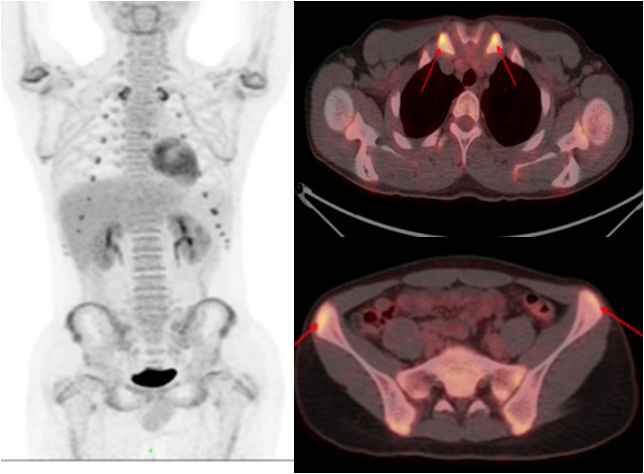

少年男性,間斷發(fā)熱半年,一直未找到原因。PET/CT 顯示多處關(guān)節(jié)、軟骨高代謝灶,最終診斷為復(fù)發(fā)性多軟骨炎導(dǎo)致的不明原因發(fā)熱,經(jīng)指導(dǎo)后臨床治療效果良好。